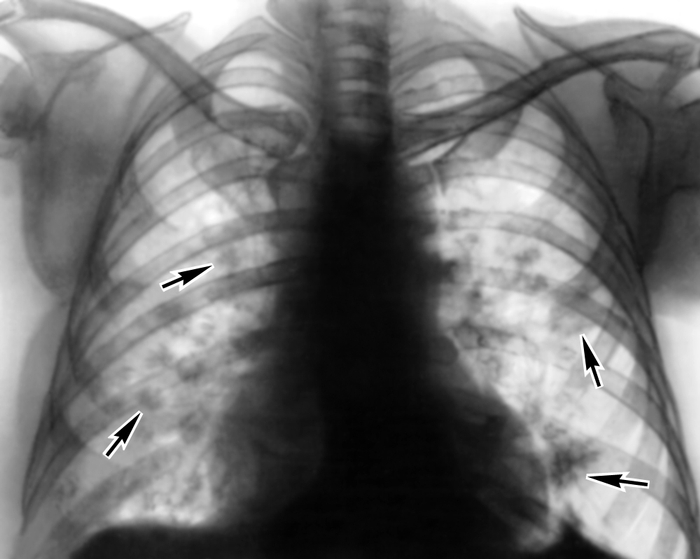

Рентгеновские снимки при пневмоцистной пневмонии